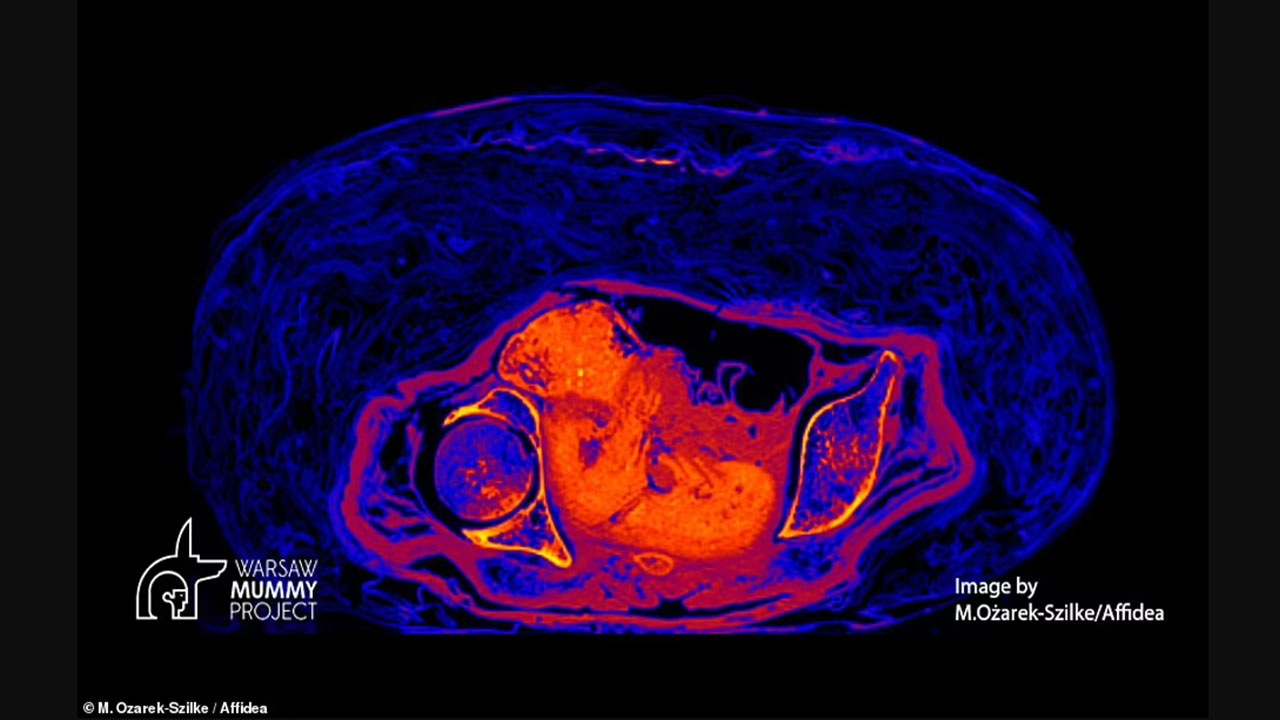

Varşova Üniversitesi bilim insanları, geçtiğimiz yıl Nisan ayında, bir mumyayı incelemeye başladı. Ekip, bilgisayarlı tomografi ve X-ray taramalarını kullanarak kadın mumyanın karnındaki doğmamış çocuğun kalıntılarını ortaya çıkardı.

Araştırmacılar, fetüsün pozisyonuna ve doğum kanalının şekline dayanarak Gizemli Hanım'ın doğum esnasında ölmediğini belirledi. Önceki araştırmalar, mumyanın öldüğünde hamileliğinin 26-30. haftaları arasında olduğunu göstermişti. 'Gizemli Hanım' ve doğmamış çocuğu üzerindeki son çalışmayı, Polonya'nın Varşova Üniversitesinden arkeolog ve paleopatolog Marzena Ożarek-Szilke ve meslektaşları yaptı.

Bilim insanları, mumyalama işleminden sonra rahim içeriği de dahil olmak üzere cesetlerdeki kan pH'ının önemli ölçüde düştüğünü, daha asidik hale geldiğini ve amonyak ve formik asit konsantrasyonlarının zamanla arttığını söylüyor. Araştırmacılar, “Vücudun natron ile dolması, hava ve oksijene erişimi önemli ölçüde sınırladı. Sonuç, fetüsün bulunduğu neredeyse hava geçirmez şekilde kapalı bir rahim.” diyor. Bilim insanları, bu durumu bataklıklardaki bedenlerin yüzyıllarca korunmasına benzetti.